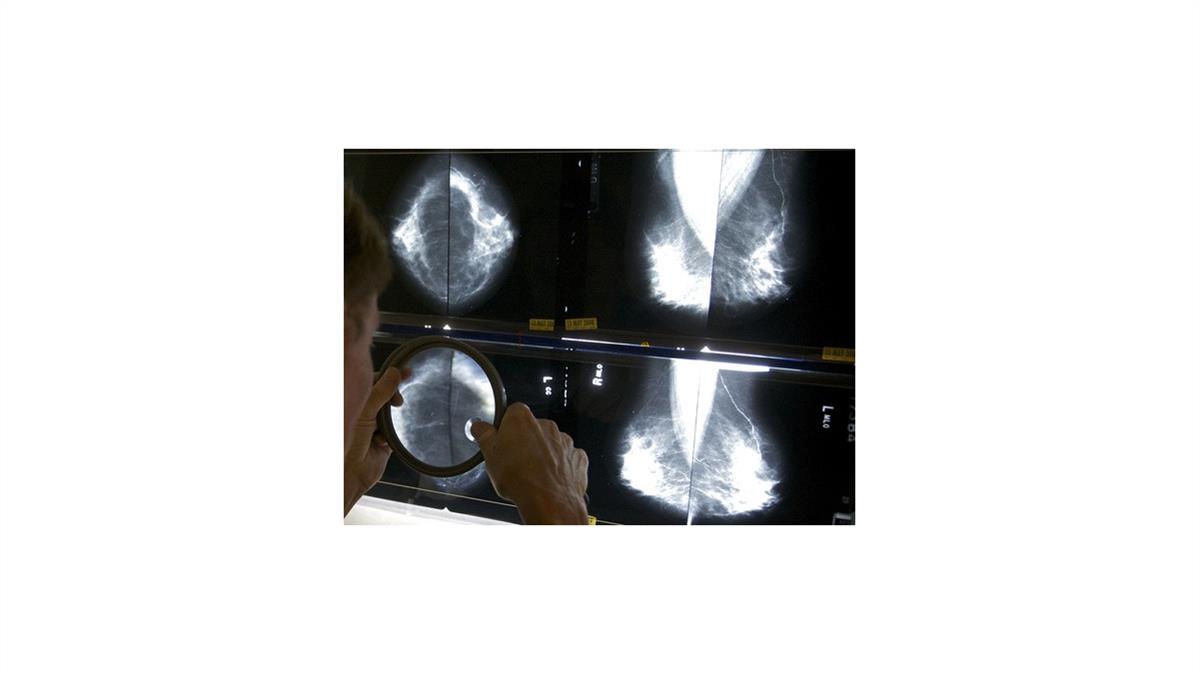

EEUU exige que se informe sobre la densidad mamaria en mastografías

Todas las estadounidenses que se realicen mastografías recibirán pronto información sobre su densidad mamaria, que a veces puede dificultar la detección del cáncer.

Aproximadamente la mitad de las mujeres mayores de 40 años tienen mamas densas, con menos tejido adiposo y más tejido conjuntivo y glandular. Ese tejido aparece blanco en las radiografías, del mismo color que los tumores mamarios, lo que dificulta la lectura de las mastografías. El tejido mamario denso es uno de los factores que puede aumentar las probabilidades de que una mujer desarrolle cáncer.

Según las nuevas normas, las mujeres con mamas densas recibirán una nota escrita alertándolas de que su estado “dificulta la detección del cáncer de mama”. También se les indicará a esas pacientes que discutan los resultados con su médico.